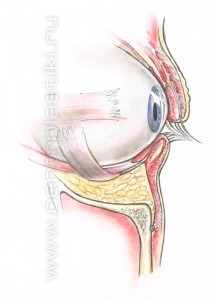

Рис. 6 Мышцу, аккуратно приподнимают и отделяют до края глазницы. Рис.7. Жировые «грыжи» опускаются вниз за край глазницы и фиксируются к надкостнице несколькими нитями, Рис. 8-9 таким образом, удается заполнить слезную и веко-щечную борозды Рис. 10.

Рис. 9 Через боковую часть разреза выполняется отделение надкостницы от костей в проекции средней зоны лица вниз до крыла носа, обычно для этого используются эндоскопические инструменты. Рис. 11 Мобилизованные ткани прошиваются в верхненаружном углу и фиксируются к надкостнице выше наружного угла глаза. Рис. 12 Выполняется миопексия (фиксация мышцы окружающей глаз) Рис. 13 и кантопексия (фиксация наружного угла глаза), Рис. 14 затем удаляется избыток кожи Рис. 15. Этим достигается правильное положение глазной щели и удается добиться разглаживания мелких морщин. В конце операции кожная рана зашивается косметичным внутрикожным швом.